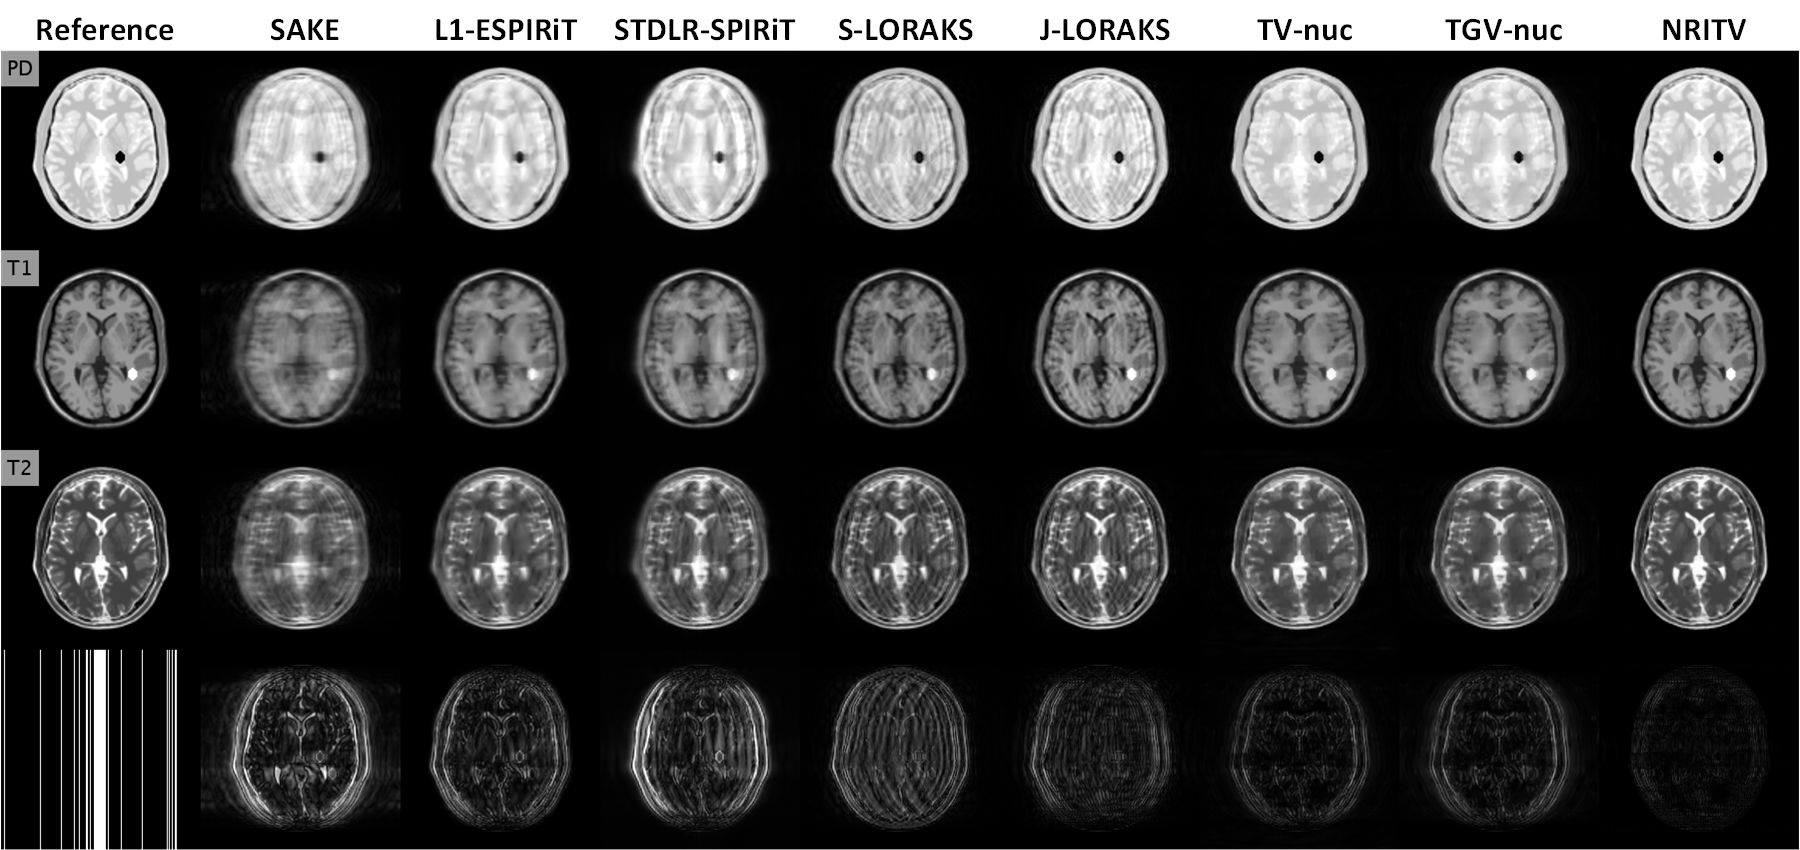

The next experiment involves reconstruction of a 4-contrast breast dataset from Cancer Imaging Archive [31] which was acquired from a 33 year old patient on a 1.5T MRI machine (GE Healthcare, Chicago, Illinois, U.S.). Sequence parameters can be seen in [31]. The 5-coil data was retrospectively undersampled at R=9𝑅9R=9 and reconstructed by all methods. Fig. 9 shows magnified views on the first 2 contrasts. The arrows in Fig. 9 mark a contrast-enhanced vessel which is highly aliased by LORAKS methods and poorly captured by the other compared works but sharply visible with the proposed one. Fig. 14 shows full FOVs for all 4 contrasts reconstructed by all methods. Table 7 gives the parameters for compared methods. In this experiment, ESPIRiT failed to produce an acceptable estimation of sensitivity maps, hence NRITV used the same maps as the SENSE-type methods.

Refer to caption

Figure 14: Full FOVs of reconstructions in Fig. 9 in the main article. The bottom row shows the sampling pattern used in the experiment as well as error maps (sum of absolute differences over all contrasts) for each method.